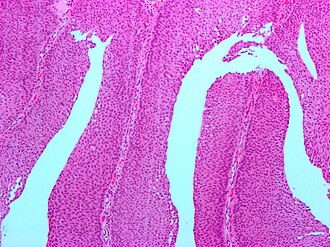

Template:Px PUNLMP. H&E stain. | |

Features:[5]

- Rare fused papillae.

- Infrequent mitoses.

- Nuclei larger than papilloma - but monotonous.[6]

PUNLMP - low mag. (WC/Nephron)